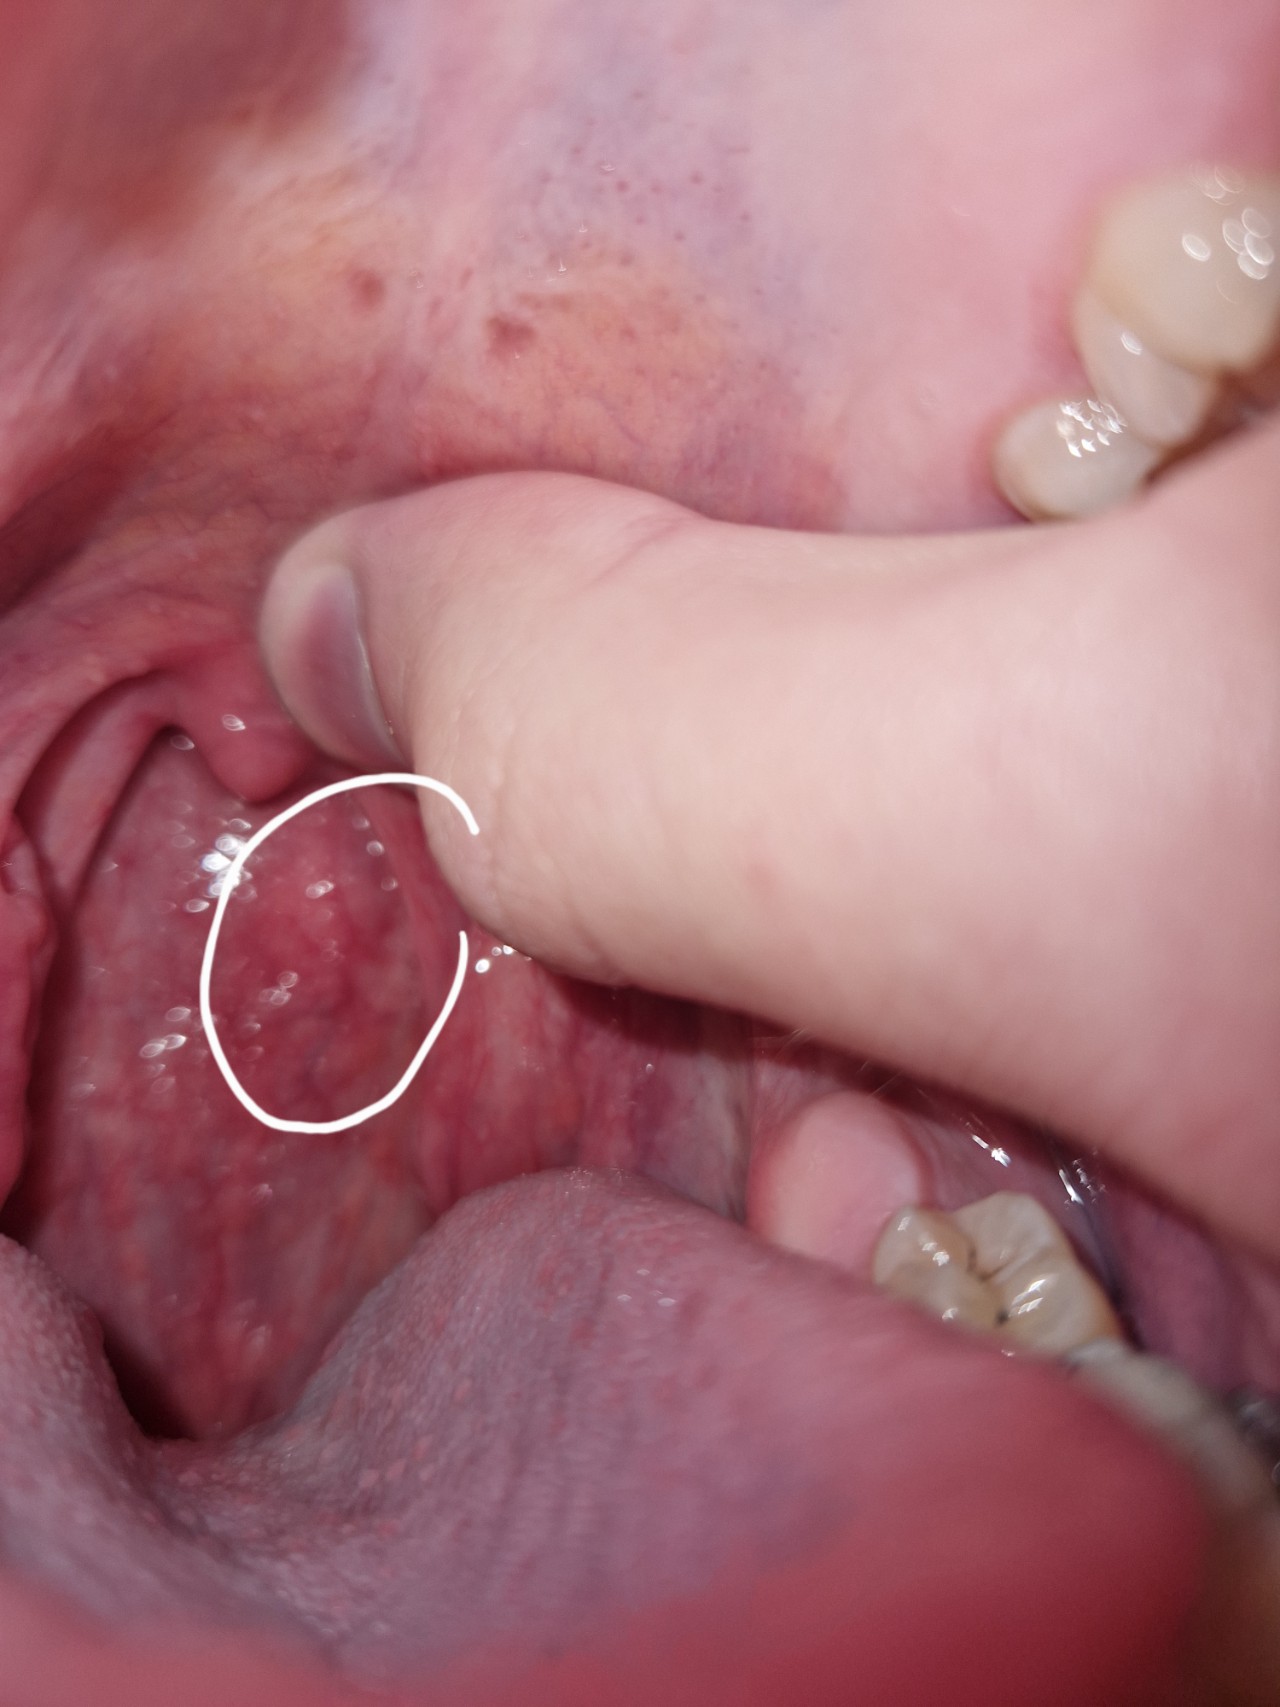

Плотное образование в ротоглотке

Здравствуйте, сегодня впервые заметил образование в области горла (визуально — на задней стенке глотки/вблизи небной дужки). На ощупь оно кажется плотным и неподвижным.

Не могу сказать, как давно оно появилось — раньше не обращал внимания. Не знаю, увеличивается ли оно и меняется ли по форме.

Боли нет, дискомфорта практически не ощущаю. Кровоточивости не было. Язв или повреждений визуально не вижу. Глотание не нарушено, голос не изменился. Слух без изменений.